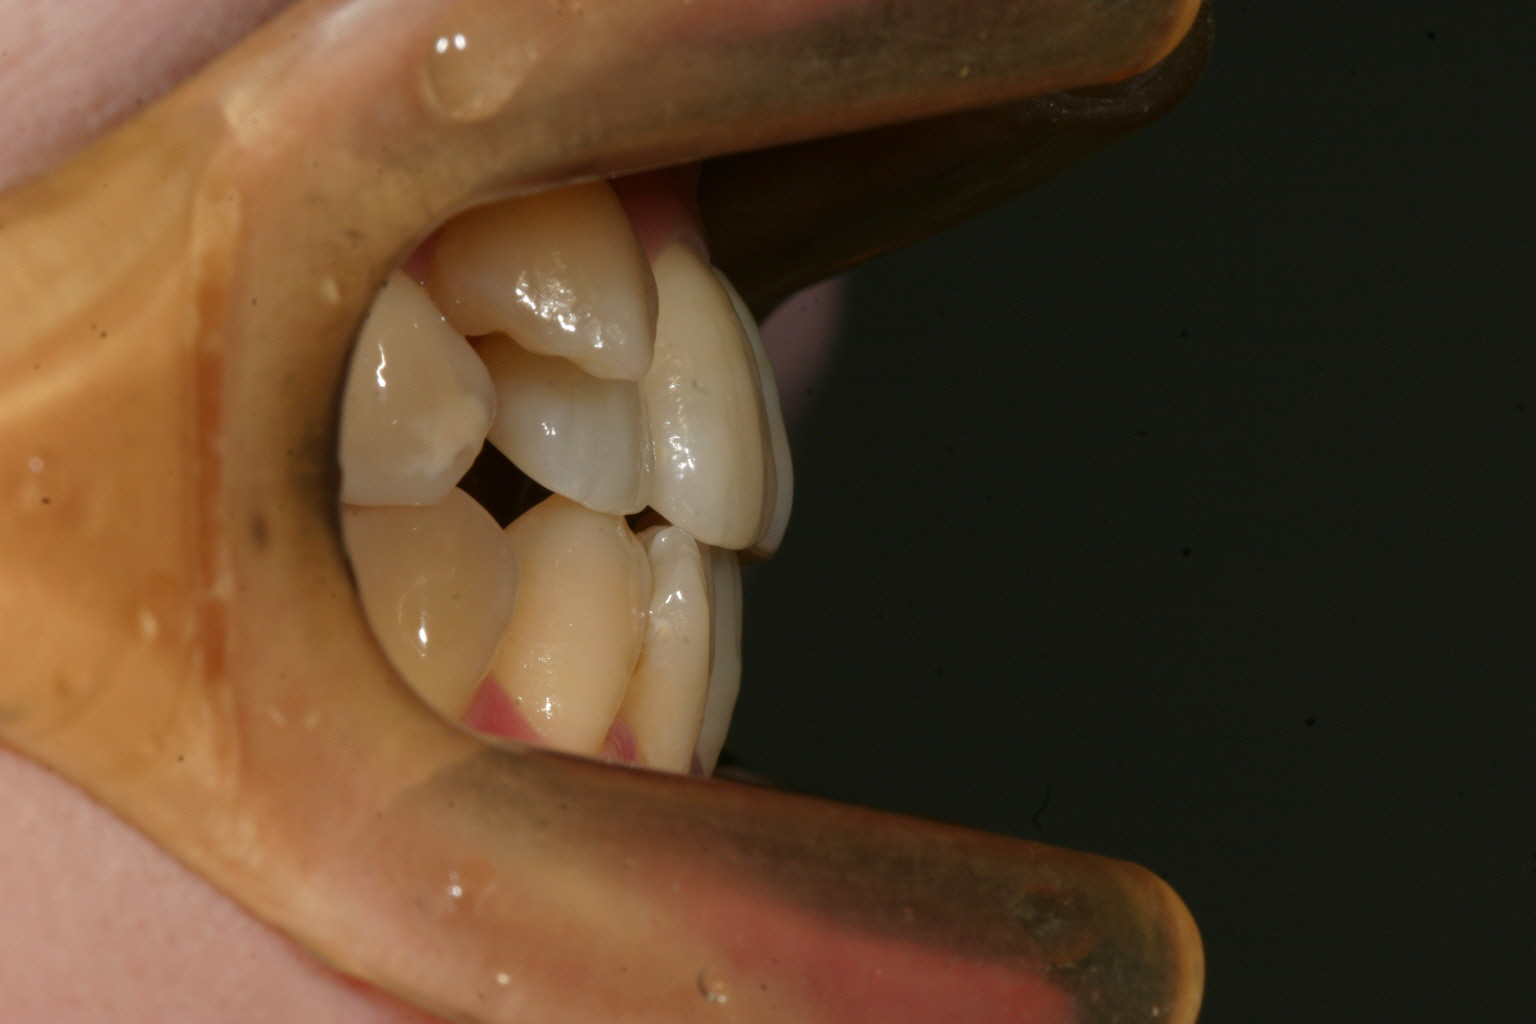

犬歯の問題だけでオーバージェット(前歯の前突)はさほど見られません。

小臼歯抜歯した後に綺麗に犬歯が入りました。

オーバージェットもバッチリです。